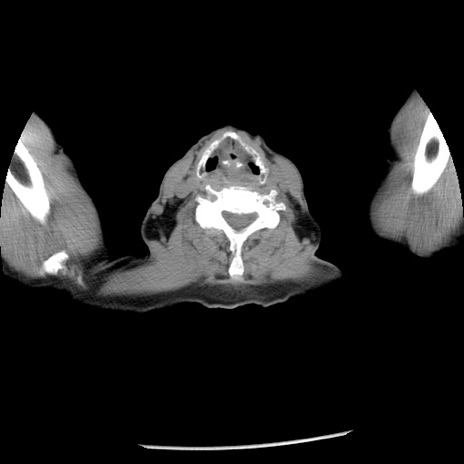

冠状断像